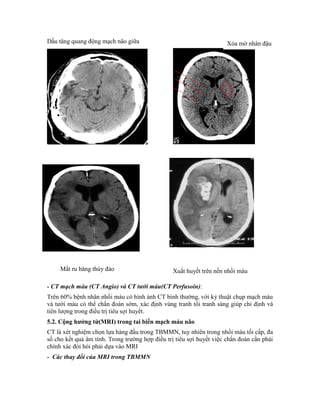

+ Các dấu hiệu sớm: có 5 dấu hiệu sớm của thiếu máu não

Dấu tăng quang động mạch có thể thấy ở động mạch não giữa, động mạch thân nền và

Xoá mờ nhân đậu: nhân đậu được cung cấp máu từ động mạch não giữa, bình thường

nhân đậu có độ cản quang cao hơn mô não, trong nhồi máu nhân đậu phù và độ cản

quang giảm bằng các vùng lân cận và không phân biệt được.

Dấu ru băng thuỳ đảo: đây là lớp vỏ não thuỳ đảo, trong nhồi máu đậm độ giảm và không

còn phân biệt lớp vỏ não này.

Xoá mờ khe sylvius: bình thường khe sylvius chứa dịch não tuỷ, trong nhồi máu thuỳ đảo

bị phù nề và lớp dịch não tuỳ giảm đi hay biến mất.

Mờ rãnh vỏ não và giảm đậm độ: đây là 2 triệu chứng quan trong do phù não gây ra.

Dấu tăng quang động mạch não giữa